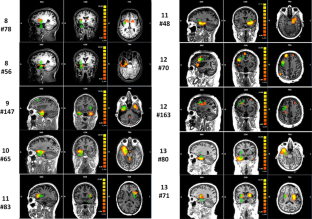

Fig. 2